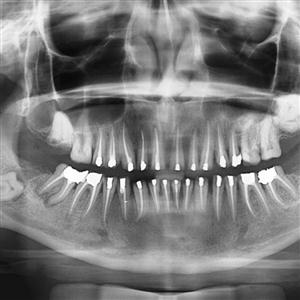

Direct Digital OPG = Special Panoramic x.ray of upper and lower teeth, mandible and T M Joints in single x.ray film by special dedicated OPG Machine.

We are using World-class Carestream Equipment 8000 C Direct Digital OPG (The first one in Saurashtra installed in 2010) with which we can take OPG film within 20 seconds in single shot. The machine produces the image directly on the monitor without cassette or screen.

This technology produces best images for better diagnosis with great patient comfort and user friendly approach.

Prescribed by Dentists, ENT Surgeons, Plastic / Maxillo-facial Surgeons and Onco Surgeons.